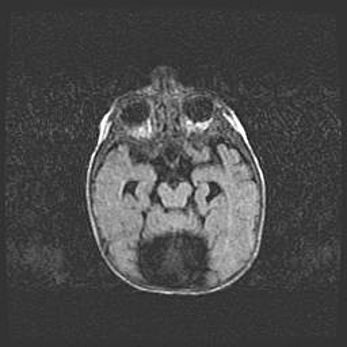

Мальформация Денди-Уокера. Киста задней черепной ямки.

Агенезия мозолистого тела.

Возраст: 2,5 месяца

Вес: 2420 г

Пол: женский

Окружность головы: 37 см

Срок гестации: 32 недели

Мальформация Денди—Уокера — редкий вид патологии ЦНС, представляющий собой врожденный порок развития каудального отдела ствола и червя мозжечка, ведущий к неполному раскрытию срединной (Мажанди) и латеральных (Лушка) апертур IV желудочка мозга. Для этогно синдрома характерна триада симптомов: гипотрофия червя мозжечка и/или полушарий мозжечка, кисты задней черепной ямки, гидроцефалия различной степени. В 70% случаев порок сочетается и с другими аномалиями головного мозга, в частности с агенезией мозолистого тела.